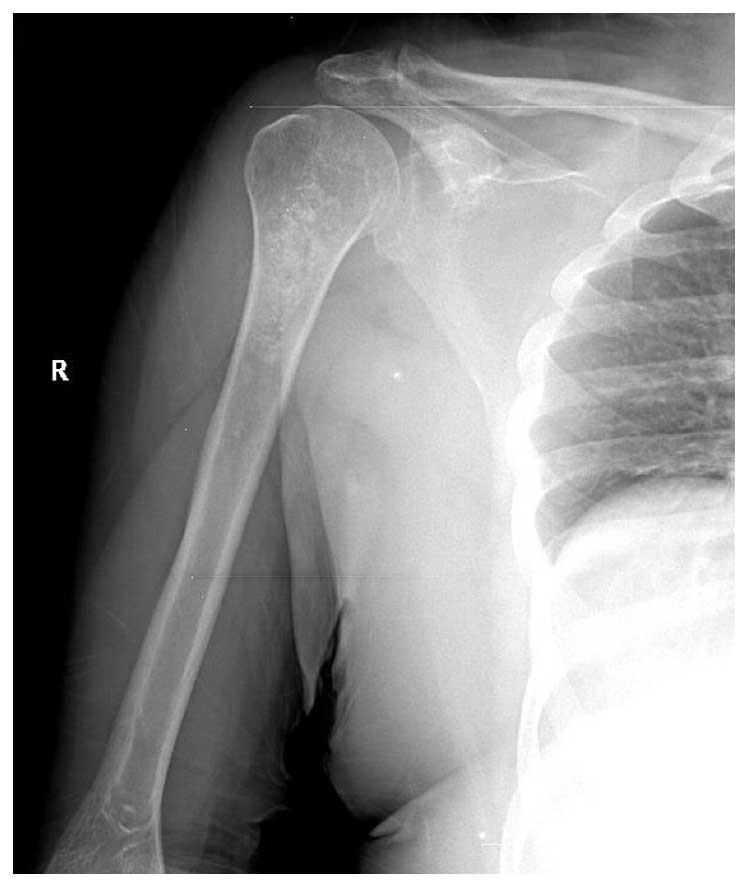

Ameliyat Öncesi: Röntgende Proksimal Humerus’ta düzensiz kalsifikasyonlar içeren tümör dokusu görülmekte.